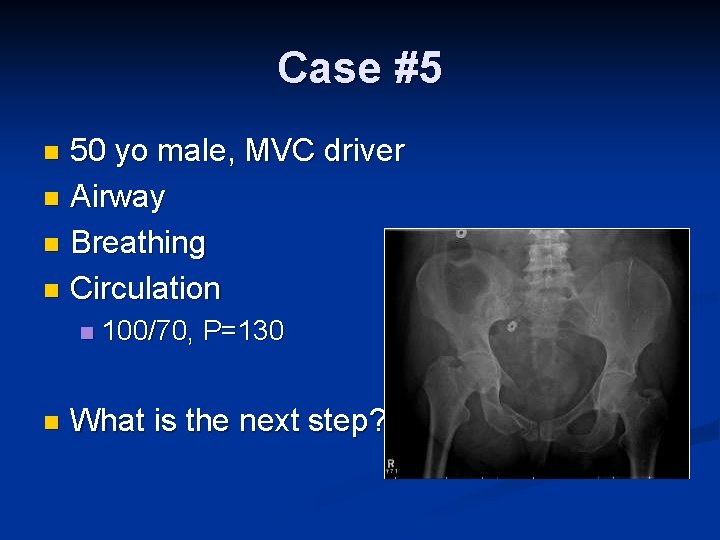

Case #5 50 yo male, MVC driver n Airway n Breathing n Circulation n 100/70, P=130 What is the next step?

Priorities ABC n Consider associated injuries with pelvic trauma n Blood vessels – arterial and venous n Bone n Bladder and urethral n Bowel n Baby (Uterus) n Other Body injuries n